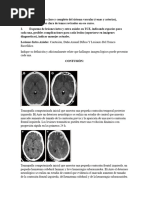

Tomografía Computada

- no puede detectar lesiones no hemorrágicas.

- sólo puede verse una hipodensidad debido a

edema .

- después que desaparece el edema, la TC

puede ser normal.

- la atenuación entre el tejido normal y

lesionado es pequeña.

Lesión Características Imagen

hemorrágica menor de 1 cm. hiperdensa

no hemorrágica mayor de 1.5 cm hipodensa

Resonancia Magnética

- Es sensible para las lesiones no hemorrágicas.

- Son necesarios T1, DP Y T2 con GRE.

- La imagen de la LAD varía con el estado de la

hemoglobina.

- EL T2 GRE es la secuencia más sensible para

detectar las lesiones.